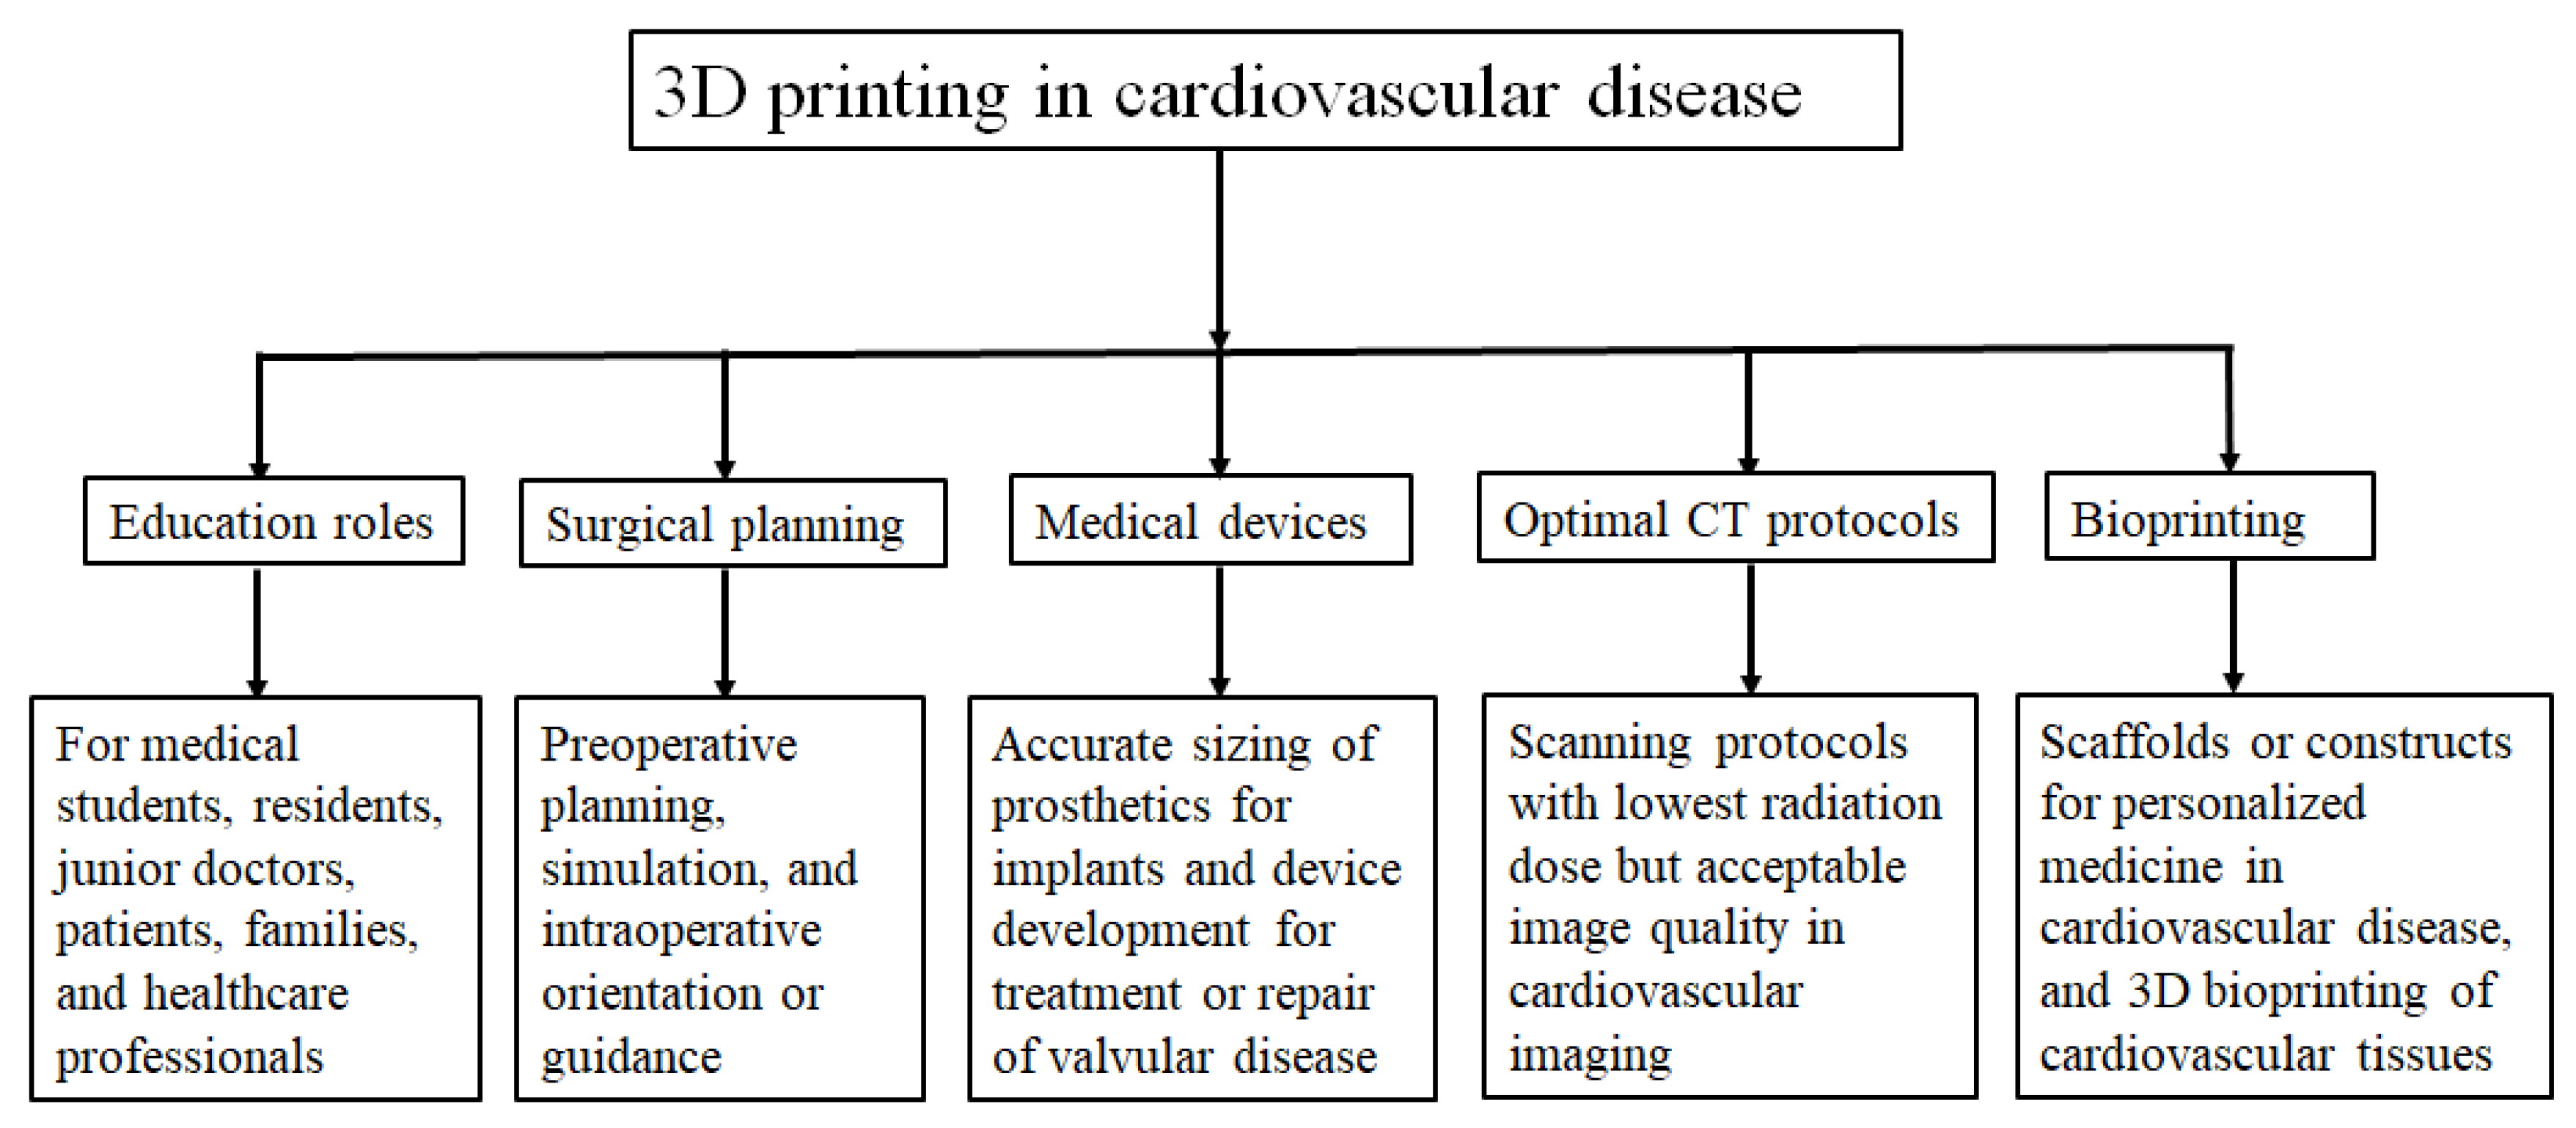

3.1. 3D Printing in Congenital Heart Disease

- Sun, Z.; Lau, I.; Wong, Y.H.; Yeong, C.H. Personalized three-dimensional printed models in congenital heart disease. J. Clin. Med. 2019, 8, 522. [Google Scholar] [CrossRef] [PubMed]

- Lau, I.; Sun, Z. Dimensional accuracy and clinical value of 3D printed models in congenital heart disease: A systematic review and meta-analysis. J. Clin. Med. 2019, 8, 1483. [Google Scholar] [CrossRef] [PubMed]

- Lau, I.; Sun, Z. Three-dimensional printing in congenital heart disease: A systematic review. J. Med. Radiat. Sci. 2018, 65, 226–236. [Google Scholar] [CrossRef]